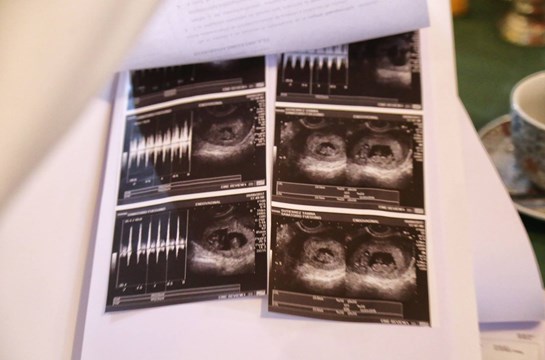

Tras enterarse de que se convertirían en padres, Yanina y Matías, que viven en Río Grande, Tierra del Fuego,fueron al médico y se llevaron una sorpresa cuando después de la ecografía el médico que los atendió se quedó en silencio y les dijo que su caso era particular: primero porque esperaban cuatro bebés y segundo porque se traaba de mellizos y gemelos a la vez.

“Sos la reina madre de la familia”, le dijo con asombro el obstetra. Y después les comunicó que se convertirían en padres de mellizos y gemelos y que su caso era prácticamente único. “Nos dijo que eran cuatro, dos gemelos en una bolsita y mellizos en dos bolsitas aparte. O sea, tres bolsitas. Un embarazo múltiple”, cuenta Matías, que dice que son papás primerizos y que cuando se enteraron de que esperaban cuatro bebés, “todo fue felicidad”.

Aunque luego de la última ecografía el médico les dijo que uno de los gemelos corre riesgo de vida, porque no llegó a desarrollarse del todo, Matías dice que siguen adelante "con toda la fuerza". “Nosotros sabíamos que era un embarazo de riesgo. Hay muchas posibilidades de que los bebés nazcan a los seis meses”, sostiene. Una vez instalados en Buenos Aires, Yanina y Matías se prepararán para la llegada de los pequeños, rodeados de todo el amor de su familia. “Si vamos a Buenos Aires la semana que viene, cuando volvamos a Río Grande, ya vamos a volver con los bebés”, se emociona Matías, en medio la expectativa y felicidad por la noticia.